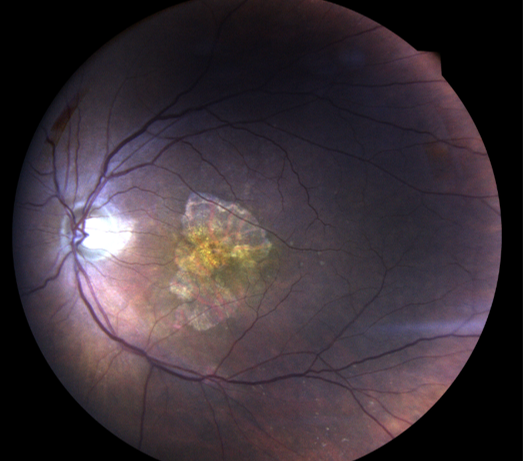

Rétinophoto couleurs montrant une DMLA exsudative avec une hémorragie maculaire et des drusen. Coupe OCT centrée sur la macula avec un œdème et des signes d’exsudation

Elle se caractérise par le développement de petits vaisseaux gorgés de sang au centre de la macula. Ces vaisseaux peuvent saigner, et créer un gonflement de la rétine appelé « œdème maculaire », entrainant ainsi la mort des photos récepteurs.